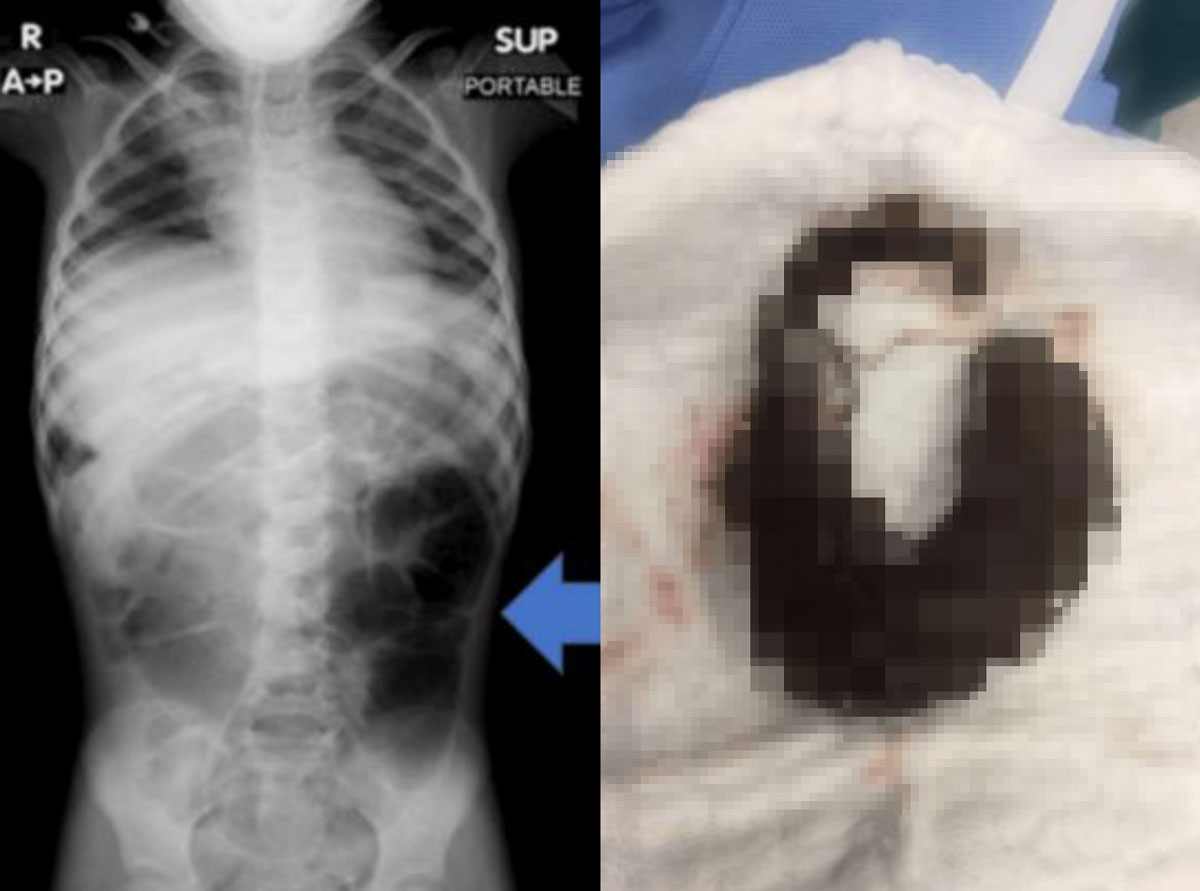

ÀÇ·áÁøÀº º¹Åë ¿µ»ó °Ë»ç¸¦ ½ÃÇàÇß°í, À§Àå ³» Å« À̹°ÁúÀÌ ¹ß°ßµÆ´Ù. Á¤Ã¼´Â ¹Ù·Î ¸Ó¸®Ä«¶ô µ¢¾î¸®¿´´Ù. ¸Ó¸®Ä«¶ô µ¢¾î¸®´Â À§¿¡¼ ¼ÒÀå±îÁö ±æ°Ô À̾îÁø ¸ð½ÀÀ̾ú´Ù.